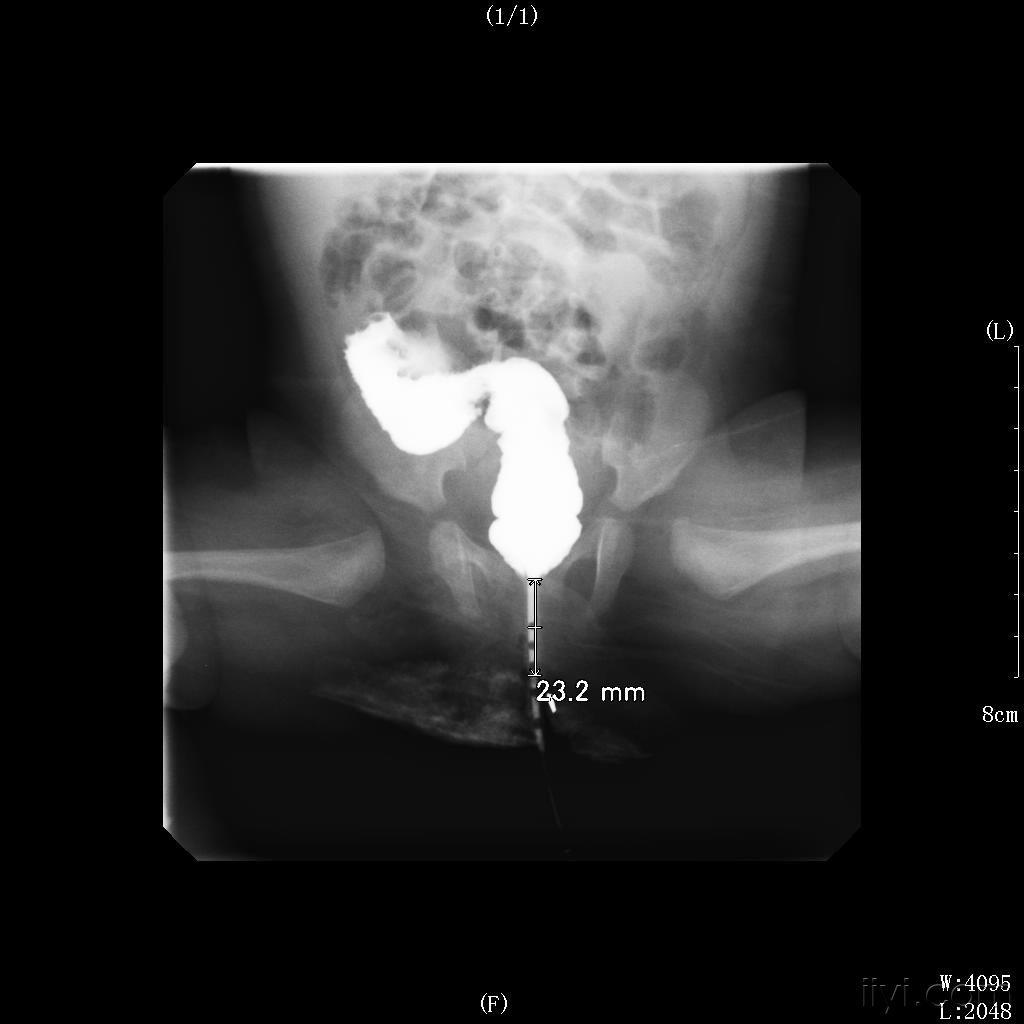

我还记得那一天,当我被诊断出患有肛门闭锁和大便失禁的时候,心情是多么的沉重和迷茫。面对这样的疾病,我感到了无比的恐惧和无助。闭锁的肛门让我感到被困住,大便失禁让我感到羞愧和尴尬。

在治疗的过程中,我经历了无数次的痛苦和挣扎,但也体会到了医护人员无私的关怀和帮助。他们用亲切的话语和细心的护理,让我感受到了温暖和安慰,让我不再感到孤独和绝望。

慢慢地,我学会了接受这个疾病,学会了坦然面对生活中的困难和挑战。闭锁的肛门并没有阻挡我前行的步伐,大便失禁也没有摧毁我内心的坚强和勇气。我开始学会珍惜每一个美好的瞬间,学会感恩身边的人和事。

虽然疾病给我的生活带来了不便和困扰,但我依然保持着乐观和坚强的态度。我相信,只要心怀希望,勇敢面对,总会迎来阳光和希望。闭锁和失禁,只是生命中的一道坎,我会用笑容和坚持去跨过它们,迎接更美好的明。